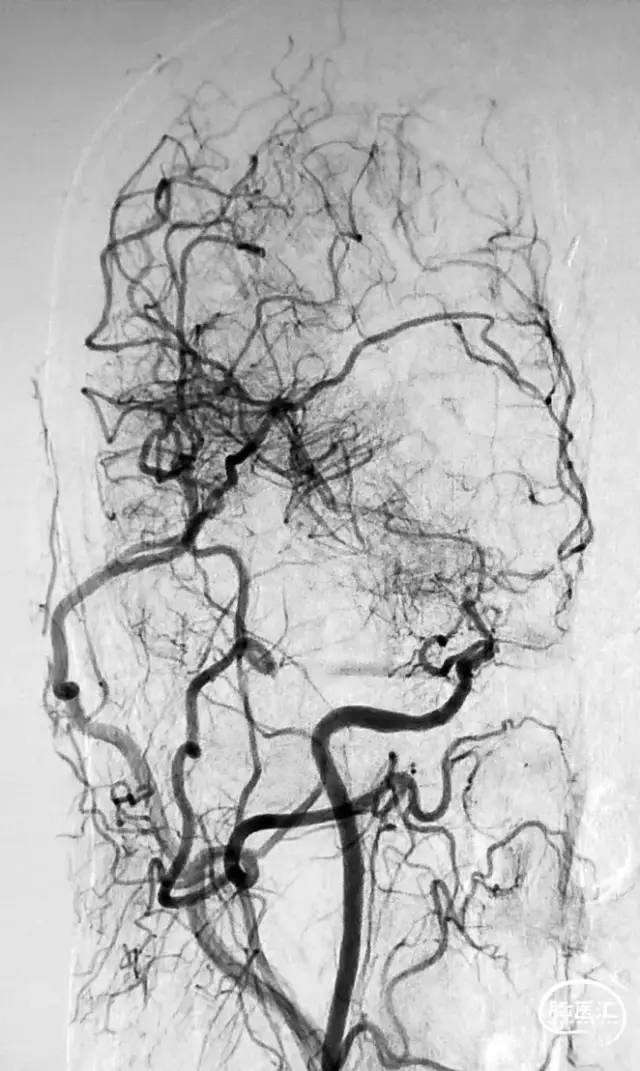

图1 从大脑后动脉(PCA)到大脑前动脉(ACA)的软脑膜侧支;A. 椎动脉注射侧位图显示ACA和PCA区域之间的逆行血流(PCA→ACA顶枕支)延伸到皮质边界区;B. 经后胼胝体周动脉经中央沟的血供。[7]